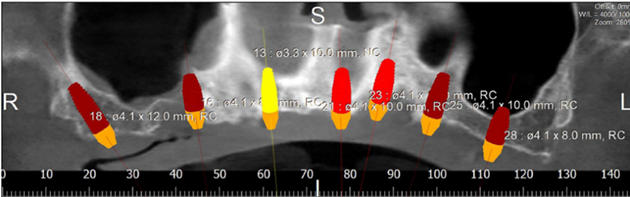

Figure 12: Panorex showing placement of 7 implants.

We chose the placement of 7 implants type Straumann without immediate loading (Figure 12). The type of the surgical guide is mucosa soft tissue supported with fixation by pins. A Flapless surgery without Bone regeneration, and a sinus Graft on 28.